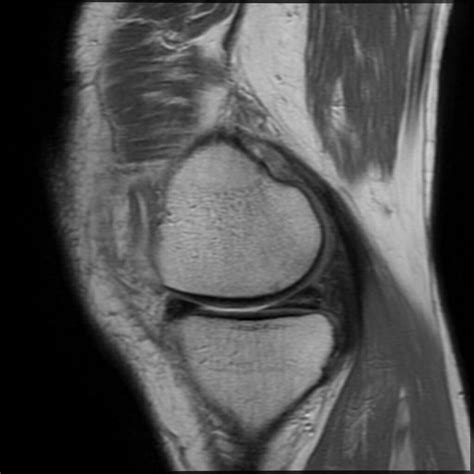

• Imaging Tests: X-rays, MRI, or CT scans may be used to visualize the bone and surrounding tissues. MRI is particularly useful for detecting bone contusions.